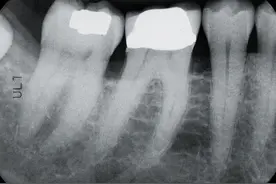

提问 葉子老师,在病房看到这个,是什么情况?请指教。这是牙齿蛀了后,长期没有得到治疗而产生的。蛀牙↓影响牙神经↓牙神经坏死↓牙神经感染↓炎症影响牙根周围的骨头↓牙根周围组织化脓↓脓水没有地方发泄↓脓水穿透骨头冲到牙床↓肿胀↓孩子经常疼痛,被无视~~那么,蛀牙应该怎么办?